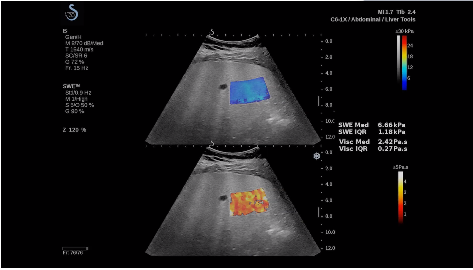

法國聲科影像(SuperSonic Imagine,SSI. Euroniex:FR0010526814)近日發(fā)表公告,宣布其研發(fā)的新一代“極速”超聲成像平臺(UltraFast Imaging),首次實現(xiàn)了肝臟的多項超聲定量評估新指標(biāo)同步檢測,包括:Att PLUS,SSp PLUS和Vi PLUS等,基本涵蓋肝臟相關(guān)病理變化指征的如纖維化、脂肪變、炎癥等。據(jù)悉,此多項新技術(shù)新將搭載于新Aixplorer系列E超系統(tǒng)。

法國聲科影像公司(SuperSonic Imagine. SA,F(xiàn)rance),2005年由三位諾貝爾獎級科學(xué)家主導(dǎo)創(chuàng)立,專注于E超的開發(fā)和生產(chǎn),是目前世界上唯一可以同時應(yīng)用兩種波進行人體檢測的系統(tǒng):縱波形成高質(zhì)量的二維組織結(jié)構(gòu)圖像,而橫波可以使醫(yī)生實時準(zhǔn)確地看到并分析組織的硬度,有效減少有創(chuàng)檢查、避免損傷。

E超相關(guān)技術(shù)已被多項多中心大樣本研究證實對于肝纖維化無創(chuàng)評估有重要意義,同時也可全面應(yīng)用于乳腺、甲狀腺、肝臟、前列腺、肌骨、婦科等全身各組織器官的定量評估和鑒別診斷。在慢性肝臟方面,聲科E超的肝臟相關(guān)定量診斷技術(shù)集,于2018年獲得美國FDA認證,成為FDA歷史上首次獲批的單病種超聲全面定量解決方案。

E超是在原有B超、彩超(彩色多普勒CDFI)基礎(chǔ)上研發(fā)成功的新一代超聲剪切波彈性成像系統(tǒng),是一種能夠全面應(yīng)用于表淺組織、腹部臟器,血管等方面的組織彈性成像技術(shù)。根據(jù)組織硬度彈性值的不同,有效鑒別實性腫瘤的良惡性。對于惡性病變的診斷具有較高的特異性和敏感性,尤其對于甲狀腺、乳腺、前列腺等小器官,能夠完成常規(guī)超聲不能完成的組織定量分析,可以實時、全幅、全定量獲得組織彈性(硬度)信息,為鑒別腫瘤的良惡性提供客觀、量化的診斷依據(jù)。